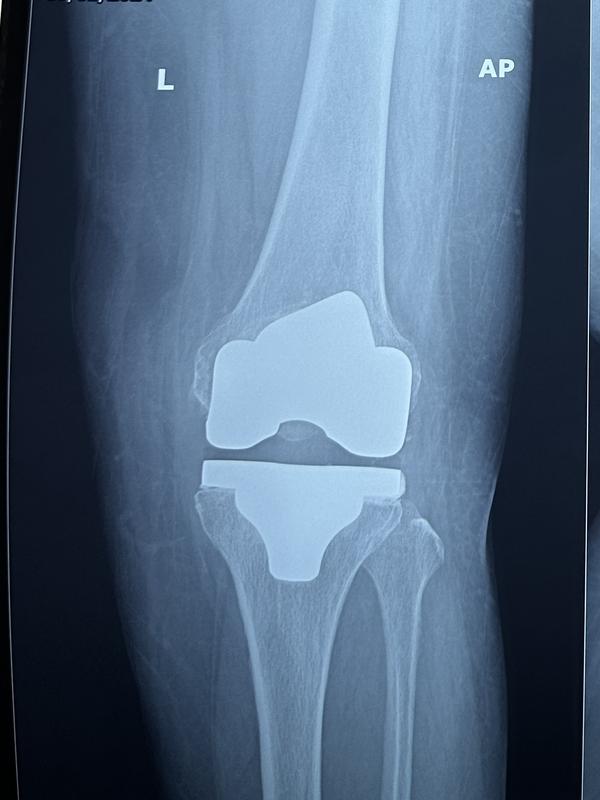

View DetailsTypes of Knee Replacement: Total Knee Replacement ...

Best Knee Replacement surgeon Total Knee Replaceme...